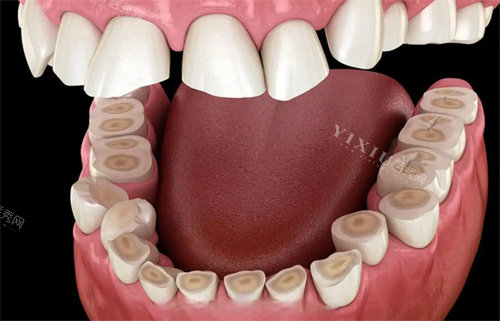

天津中牙口腔位于天津市南开区中南道南侧中南广场东区一号楼3层,交通便利,周边配套设施完善。作为一家口腔专科医院,中牙口腔拥有正规医疗执业资质,诊疗范围涵盖口腔全科项目,包括牙体牙髓病、牙周病、口腔粘膜病、儿童口腔、口腔颌面外科、口腔修复、口腔正畸、口腔种植及预防口腔等多个可靠领域。

中牙口腔在多个口腔专科领域具有显著优势,尤其以下项目备受患者好评:

5. 美学修复与全口重建

对于牙齿缺损、变色、形态不佳等问题,医院提供全瓷冠、贴面、嵌体等美学修复方案,结合智能化设计,实现自然美观的修复结果。全口咬合重建则针对复杂咬合问题,通过系统评估制定个性化修复计划。